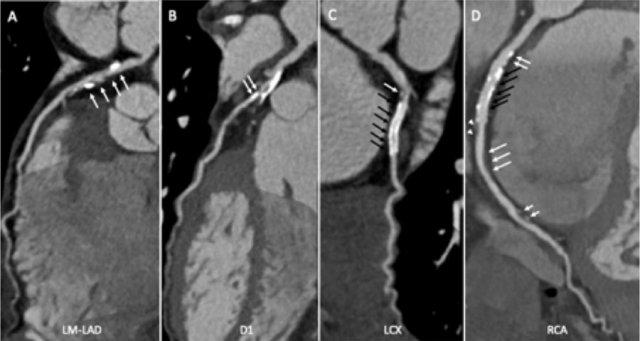

The findings are:

- Long, partially

calcified plaque in the LM-LAD causing moderate stenosis (50-69%) (white

arrows).

This segment of the LAD is difficult to evaluate because of blooming and step

artefacts. - Calcified plaque in

the D1 causing severe stenosis (70-99%) at the origin (white arrows). - Partially calcified

plaque proximal from the LCX stent with moderate (50-69%) stenosis (white

arrow).

LCX stent patent, no stenosis (black arrows). - Calcified plaques

in the proximal RCA with minimal stenosis (<25%) (white arrows).

RCA stent patent (black arrows).

Non-calcified plaque distal to the stent causing minimal stenosis (white

arrowheads).

Another non-calcified plaque in the distal RCA causing minimal stenosis

(<25%) (white arrows).

Partially calcified plaque in the distal RCA with mild stenosis (25-49%) (two

white half-arrows). - Total plaque burden

is extensive (P4).

Due to severe stenosis in D1, extensive plaque burden, some

non-diagnostic segments and a stent this patient classifies as CAD-RADS

4A/P4/N/S, which means that this patient needs further workup.

The ICA shows some wall irregularities to a maximum of 30% stenosis in

the proximal LAD.

The D1 shows 50% stenosis at the origin (black arrows). The LCX shows some wall

irregularities with no in-stent restenosis.

The RCA shows minimal wall irregularities, no in-stent restenosis.

This case also shows that CTA is limited in case of calcium and it can

overestimate the actual luminal stenosis.